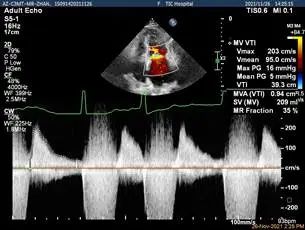

夹子放置后二尖瓣口平均跨瓣压差:1mmHg

肺静脉血流频谱恢复正向

x-plane验证前后叶抓捕后bond明显